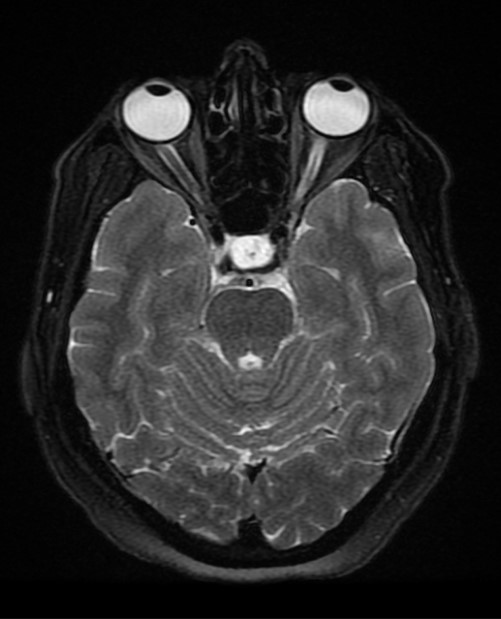

- МРТ сосудов головного мозга: очаги демиелинизации, интракраниальная патология (опухоли, абсцессы, кисты головного мозга, гематомы);

- МРТ орбиты: сдавление орбитальной части ЗН;